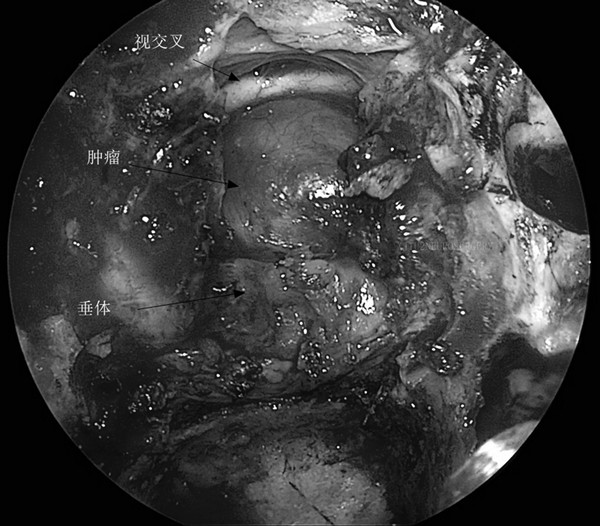

在屈建强主任的支持下,经过充分细致的准备,于2021年11月22日,与麻醉手术科刘鹏斌教授、赵梦溪、熊哲、杨欢欢等合作,吕健主任医师、王举波主治医师、肖俊医师、宋琴等在全麻下为患者施行了内镜经鼻扩大颅底入路鞍区肿瘤切除术。手术中,应用神经内镜,经双侧鼻腔抵达颅底,磨除鞍底、鞍结节和蝶骨平台后部骨质,剪开硬脑膜,见肿瘤位于视交叉后、第三脑室底与垂体之间,沿垂体柄全长生长,上端与视交叉及第三脑室底部附着紧密。肿瘤呈实体性,质地韧硬不均匀,广泛钙化,先瘤内减容,再分离包膜,肿瘤次全切除,用自体脂肪、人工硬膜、带蒂鼻中隔黏膜瓣重建颅底。手术顺利,麻醉满意,出血不多,未输血。术后患者恢复顺利,有多饮多尿,但数日后恢复正常,无脑脊液鼻漏,已出院。组织病理学检查证实了颅咽管瘤之诊断。

术中